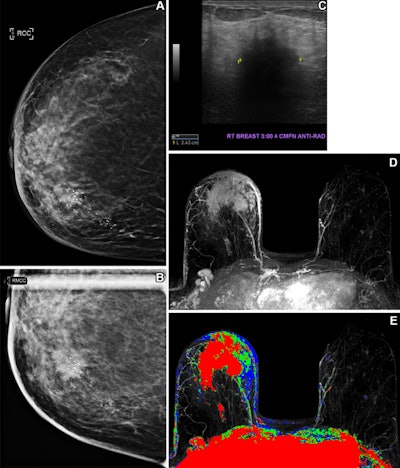

Health insurance coverage influences breast cancer screening behavior. In one case, a 61-year-old uninsured woman with no known previous screening for breast cancer presented for screening mammography. (A) A craniocaudal two-dimensional synthetic mammogram of the right breast shows an irregular mass in the medial breast with pleomorphic calcifications extending posteriorly. (B) A craniocaudal magnified mammogram more clearly shows the

irregular mass and pleomorphic calcifications in the medial breast. (C) An anti-radial ultrasound image of the right breast shows an irregular hypoechoic mass with indistinct margins and posterior acoustic shadowing at the 3 o'clock position, approximately 4 cm from the nipple. (D) An axial postcontrast maximum intensity projection (MIP) subtracted MR image shows a large enhancing mass in the anterior and medial right breast with skin thickening and enhancement and several morphologically abnormal right axillary lymph nodes. (E) An axial postcontrast MIP subtracted MR image with color mapping shows the rapidly enhancing mass with washout kinetic enhancement in the anterior and medial right breast, with skin thickening and enhancement and several morphologically abnormal right axillary lymph nodes. Histopathologic biopsy results demonstrated invasive mammary carcinoma with metastatic disease in a right axillary lymph node. Image courtesy of Peter Abraham, MD, et al.